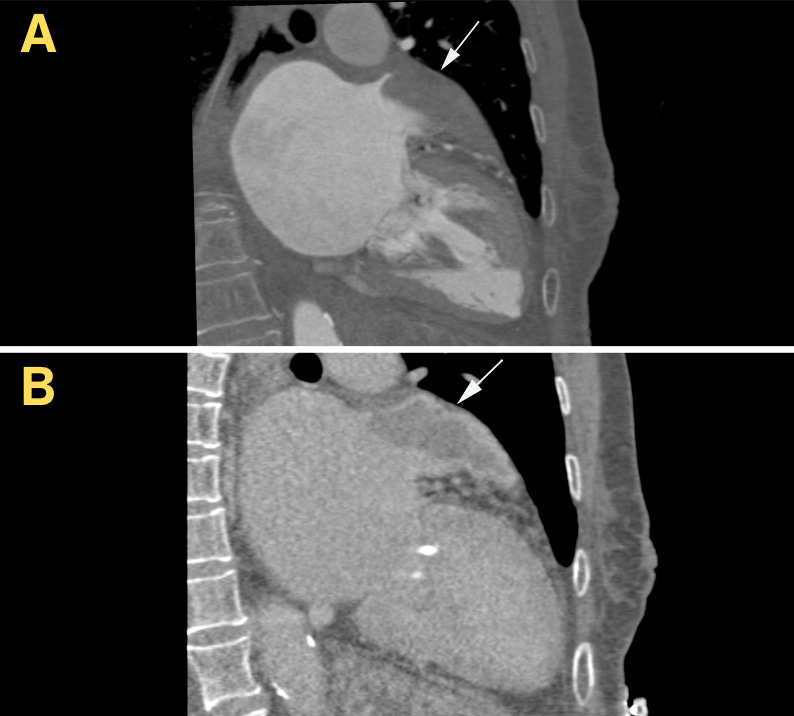

Imagem da semana

Angiotomografia do coração no planejamento de oclusão do apêndice atrial esquerdo (AAE)... e uma surpresinha: um trombo enorme ocupando boa parte da estrutura.

A dica clínica é valiosa: sempre que houver uma falha de enchimento no AAE, é fundamental realizar uma fase tardia (cerca de 1 a 2 minutos após a injeção do contraste). Isso ajuda a diferenciar se a falha é apenas resultado de enchimento lento, que desapareceria na fase tardia, ou se estamos realmente diante de um trombo, que se mantém ou até se torna mais evidente nessa fase.

💭 O que fazer agora em relação ao planejamento da oclusão do AAE? Está contraindicado?